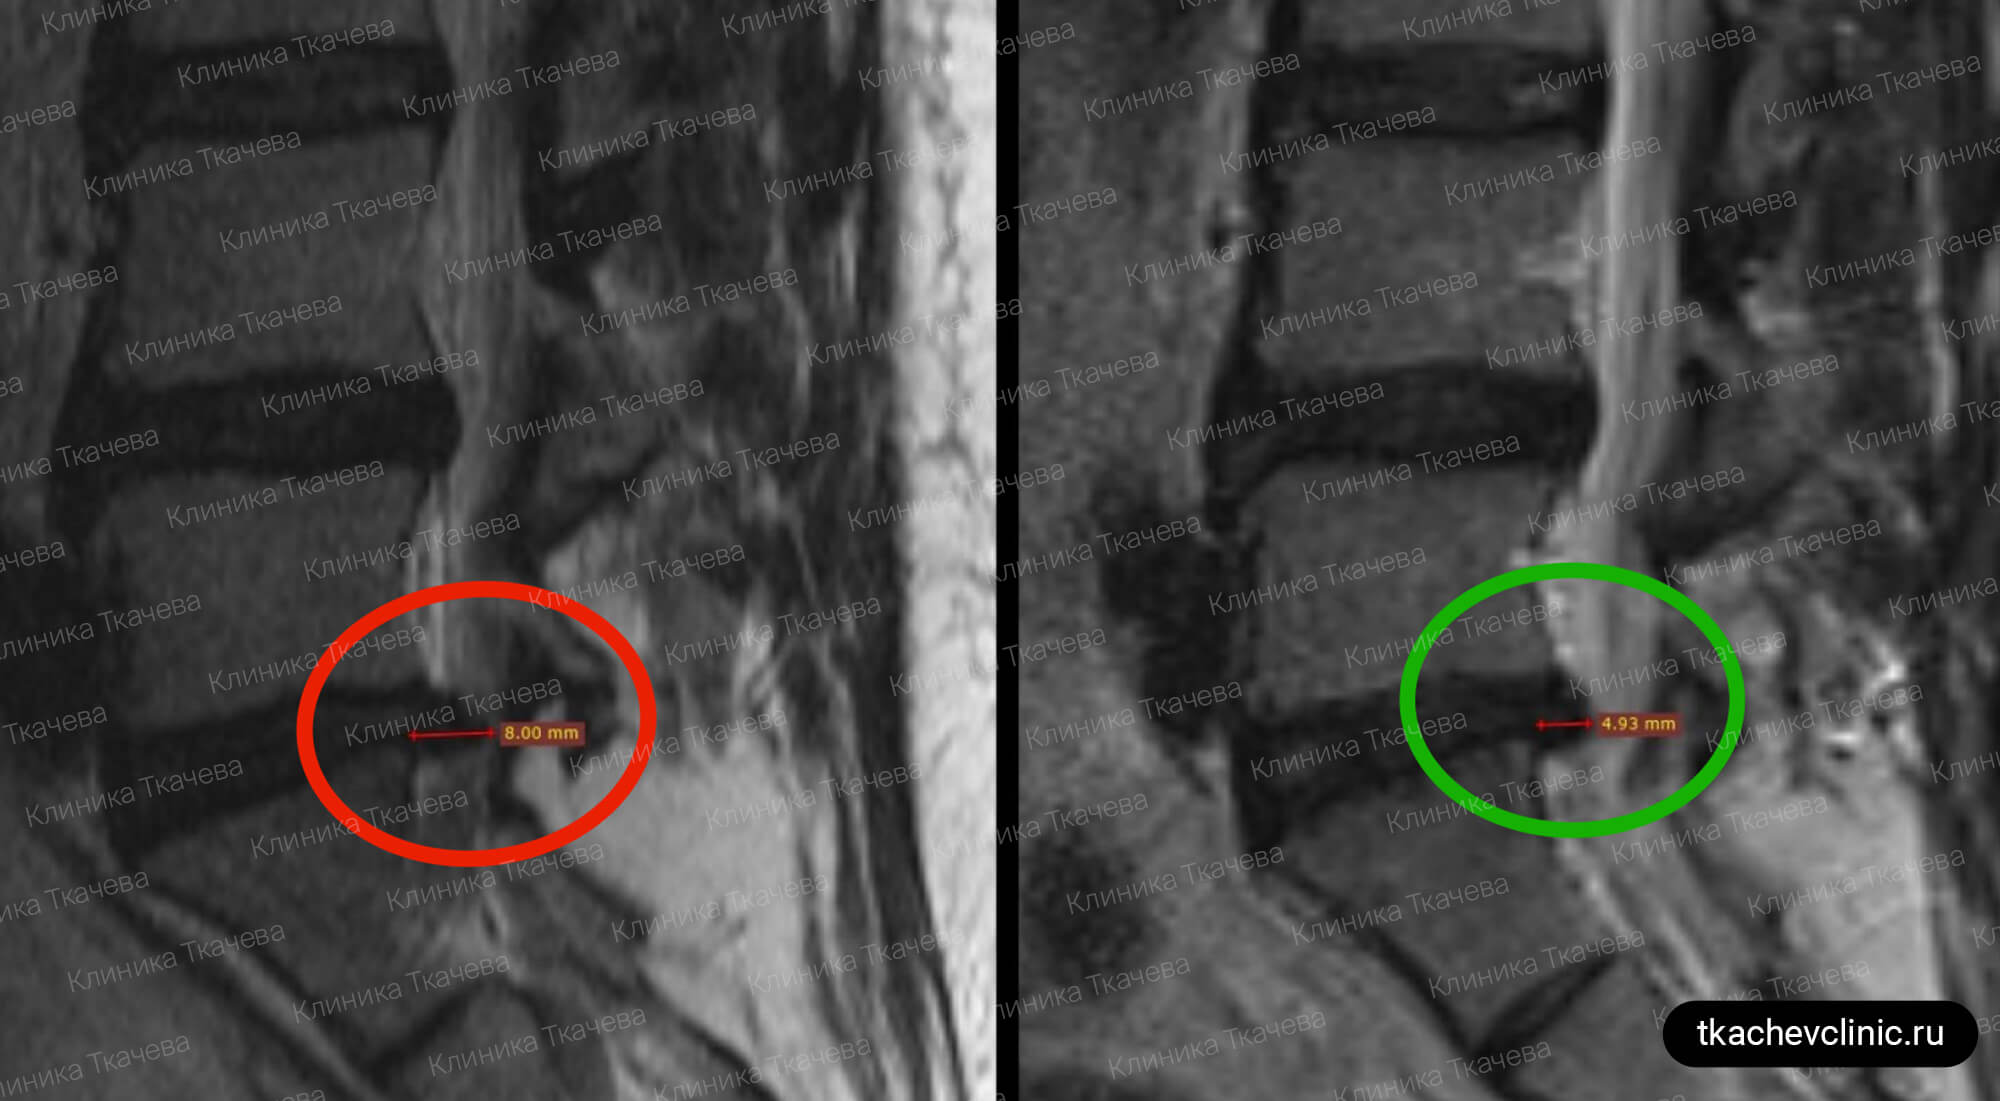

Грыжа Диска L5 S1 Фото

Грыжа Диска L5 S1 Фото 108 фотографий